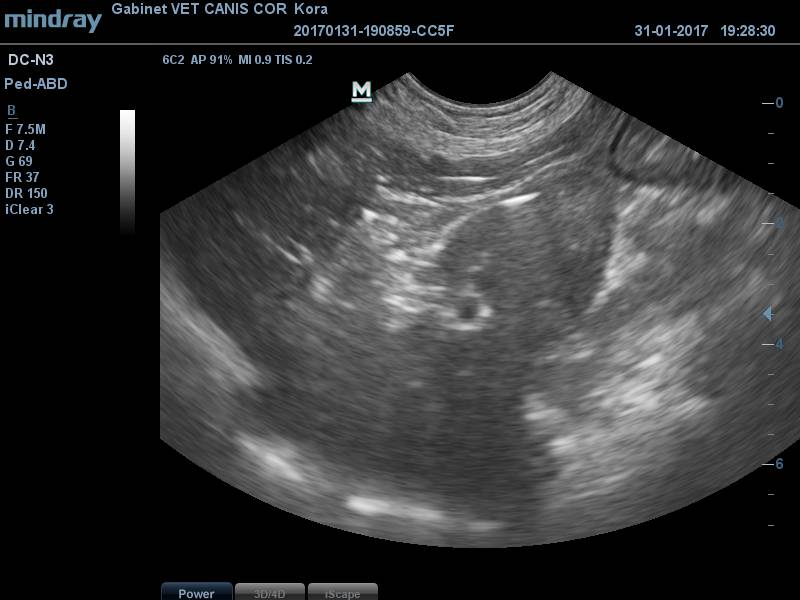

usg_dla_zwierzat.jpgJest to nieinwazyjne badanie, które ułatwia diagnostykę narządów jamy brzusznej i miedniczej (wątroba, śledziona, nerki, żołądek, jelita, macica, prostata, jajniki, pęcherz moczowy), można ocenić ilościowo płyn w jamie brzusznej.

Pomaga w określeniu zmian związanych ze skórą i podskórzem, mięśniami, gruczołami mlekowymi. Dysponujemy bardzo nowoczesnych aparatem MINDRAY DC N3 o możliwościach zbadania bardzo małej zmiany około 1 cm, a także dużych struktur położonych w jamach ciała. Posiada on funkcje doplera kodowanego kolorem, power dopler i przepływowego, co ułatwia ocenę ukrwienia poszczególnych struktur.

Jest to bardzo dobra metoda oceny ciąży, na obecność płodów suczki badamy po 21 dniu, a kotki po 25 dniu od krycia.

Wykonujemy dokumentację badania na płytce CD, którą otrzymuje właściciel.